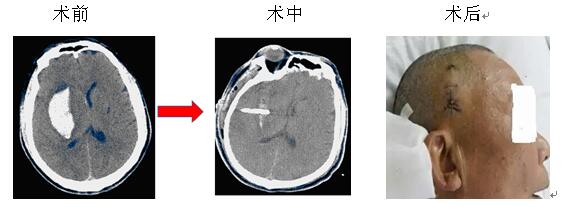

微創(chuàng)治療腦出血是指在CT或立體定向引導(dǎo)下,找到離血腫中心最近的位置,同時避開重要的組織,用YL-I型針管一體裝置在電驅(qū)動下安放引流管、抽吸血凝塊,減少血腫體積,達到清除血腫的目的。此方法創(chuàng)傷微小,操作快捷,費用較低,在有CT的醫(yī)療器械情況下即可實施,故對廣大病患,特別是老年多病的腦出血患者而言是一種不二的選擇。

院神經(jīng)內(nèi)科率先在衡陽地區(qū)實施微創(chuàng)治療腦出血,現(xiàn)經(jīng)救治的病患已達3000余人次,絕大部分患者得到好的結(jié)果,較少的死亡率,較輕的致殘率。本院將繼續(xù)提供較好的治療和服務(wù),來滿足病友的需求,也歡迎病友垂詢。